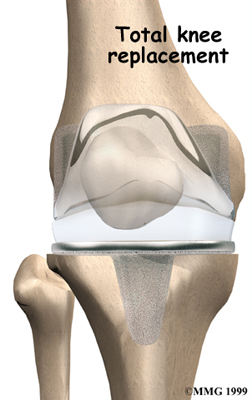

Artificial Knee Replacement

An artificial knee replacement is the ultimate solution for advanced knee OA.

Surgeons prefer not to put a new knee joint in patients younger than 60. This is because younger patients are generally more active and might put too much stress on the joint, causing it to loosen or even crack. A revision surgery to replace a damaged prosthesis is harder to do, has more possible complications, and is usually less successful than a first-time joint replacement surgery.

Related Document: FYZICAL Eastlake's Guide to Artificial Joint Replacement of the Knee